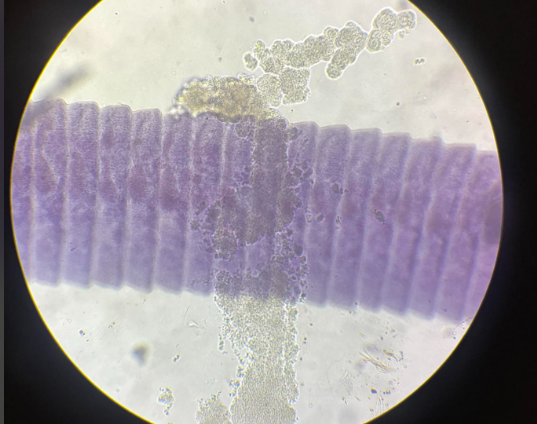

taenia saginata proglotyd przejrzały